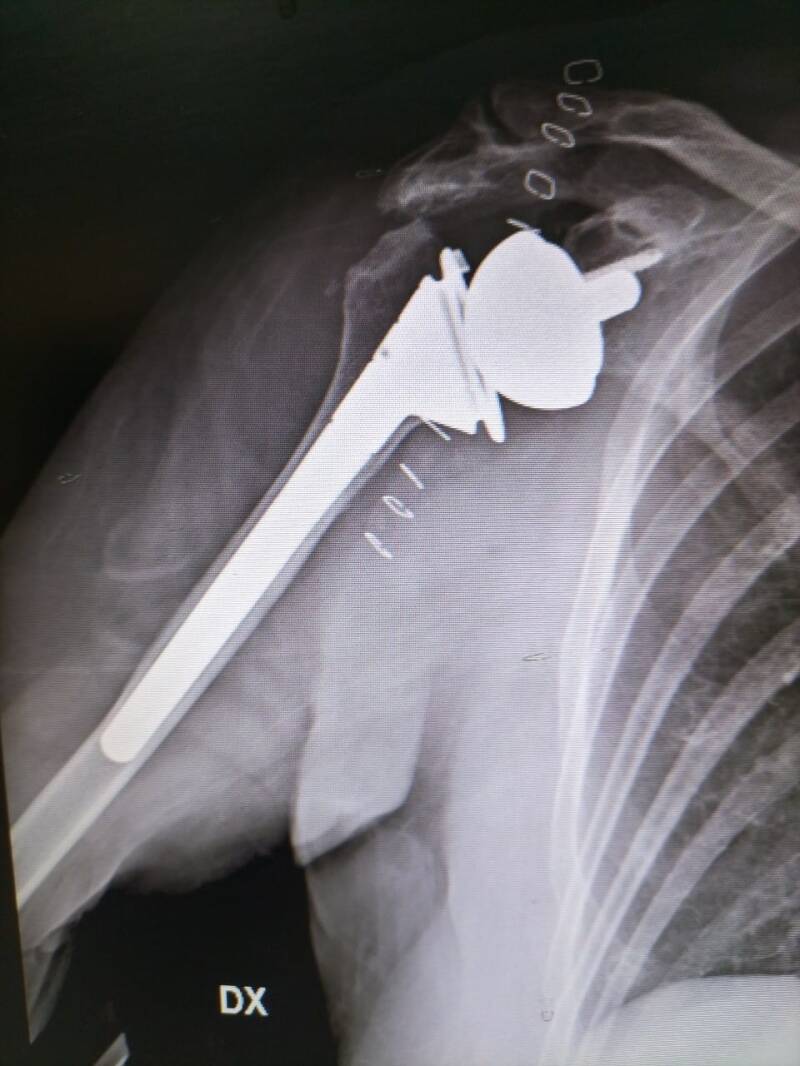

Una protesi inversa di spalla prevede di impiantare nella glenoide, una sfera metallica e di fissare una coppa con stelo protesico con inserto in plastica (polietilene) all’estremità superiore dell’omero.

Questo tipo di protesi viene impiantata per fare in modo che i movimenti per muovere la spalla e il braccio siano affidati al muscolo deltoide e non alla cuffia dei rotatori.

In questo modo anche chi ha avuto un problema di rottura dei tendini della cuffia potrà muovere il braccio in modo autonomo.

Durante l’intervento viene, dunque, impiantata una protesi di sintesi meccanica biocompatibile, che può essere di diversi modelli:

- inset (modello classico);

- onset (con componente omero lateralizzante che appoggia sull’osteotomia del collo anatomico dell’omero);

- con componente glenoidea lateralizzante.

L’intervento prevede anche di abbassare e medializzare il centro di rotazione allungando il deltoide. Allungando le fibre del muscolo deltoide si migliora il braccio di leva e il momento d’azione permettendo una mobilità completa e migliore dell’articolazione della spalla.

È possibile intervenire anche con una protesi di spalla a stelo corto o mininvasiva, in cui l’ingombro metallico è ridotto al minimo così da preservare il tessuto per successivi interventi.